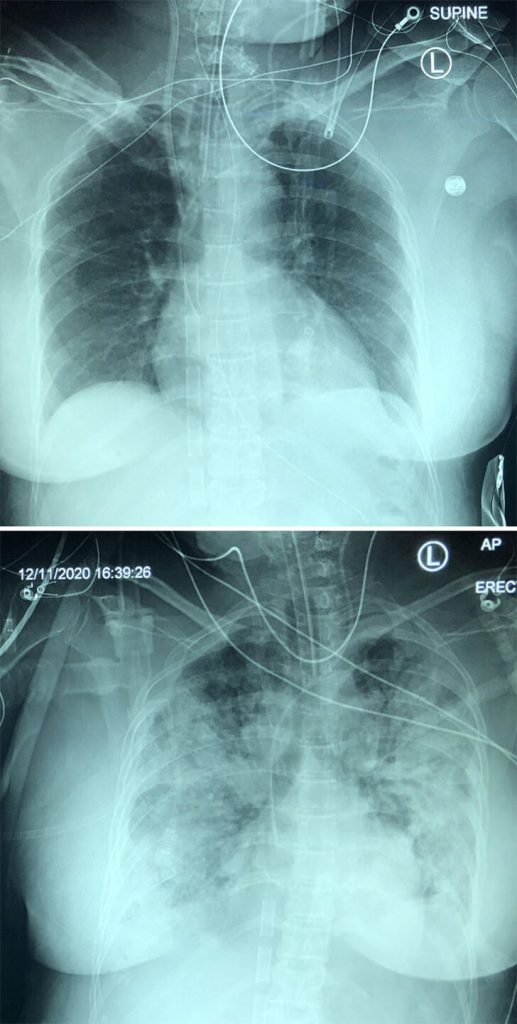

Covid-19’s Hidden Progress Caught on Camera

Ever seen a cold in action? You’re in luck because this X-ray series shows a five-day journey of COVID-19 pneumonia. It’s like a fast-forward movie but inside someone’s lungs! Day one starts quietly, but by day five, it’s a whole different story.

The X-rays get cloudier as pneumonia spreads, like a storm brewing in the chest. It’s a reminder of how sneaky this virus can be, turning our lungs into a battleground. Fascinating, yet a bit eerie, isn’t it? Science sure has some cool tricks up its sleeve!

A COVID Reality Check

This X-ray tells a starkly different story than the one a doctor’s friend tried to paint. Just hours earlier, they said, “COVID isn’t that bad.” But here’s the reality: the lungs of a COVID-19 patient, clouded and struggling.

It’s visual proof that this virus doesn’t play by the rules of downplay. COVID-19 can cause severe lung damage, a fact that this image silently screams. It’s more than a medical snapshot; it’s a wake-up call to the seriousness of the pandemic, a rebuttal in black and white against underestimation.